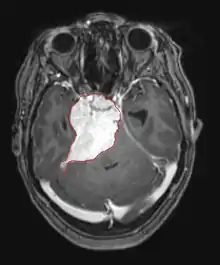

La tomodensitométrie (TDM) et L'imagerie par résonance magnétique (IRM) peuvent détecter efficacement une néoplasie dans le cerveau. L'IRM est plus sensible que la TDM pour identifier les lésions, mais présente des contre- indications pour les patients porteurs de stimulateurs cardiaques, de prothèses incompatibles, de clips métalliques et contre-indications. La TDM reste la méthode de choix pour détecter les calcifications au sein des lésions ou les érosions osseuses de la calotte ou de base du crâne. L'utilisation d' agents de contraste, iodés dans le cas du scanner et paramagnétiques (gadolinium) dans le cas de l'IRM, permet l'acquisition d'informations sur la vascularisation et l'intégrité de la barrière hémato-encéphalique, une meilleure définition de la tumeur tumorale par rapport à l' œdème environnant et à la génération d' hypothèses sur le degré de malignité. L'examen radiologique permet également d'évaluer les effets mécaniques et les modifications importantes des structures cérébrales résultant de la tumeur, telles que l' hydrocéphalie et les hernies, dont les effets peuvent être fatals. Enfin, en préparation à la chirurgie, ce diagnostic peut être utilisé pour déterminer la localisation de la lésion ou l'infiltration de la tumeur dans des zones vitales du cerveau. À cette fin, l'IRM est plus efficace que la tomodensitométrie car elle peut fournir des images en trois dimensions.

Les outils d'imagerie radiologique diagnostique mettent en évidence la modification du tissu néoplasique par rapport au parenchyme cérébral normal (par le biais de modifications de la densité tissulaire imagée électroniquement en TDM et de l'intensité du signal en IRM). Comme la plupart des tissus pathologiques, les tumeurs sont également reconnaissables par une accumulation accrue d'eau intracellulaire. Dans la tomodensitométrie, ils apparaissent hypodenses, c'est-à-dire de moindre densité que le parenchyme cérébral, dans la tomographie par résonance magnétique nucléaire avec relaxation spin-réseau hypointense et en relaxation spin-spin ainsi que l' hypersignal en pondération protonique (PD).

La tomodensitométrie du cerveau montre généralement une masse tissulaire qui peut être améliorée par l'un ou l'autre contraste. Au scanner, les gliomes de bas grade apparaissent généralement isodenses au parenchyme normal et peuvent donc ne pas présenter de rehaussement de contraste. De même, les lésions de la fosse crânienne postérieure sont difficiles à identifier au scanner. Par conséquent, les seuls résultats d'une telle tomographie ne sont pas toujours suffisants à des fins diagnostiques. Dans les cas douteux, l'utilisation de l'imagerie par résonance magnétique plus sensible est indispensable.

Sur-L'IRM montre une tumeur intracrânienne comme une lésion massive qui peut devenir plus luminescente après utilisation du produit de contraste. Cependant, il y a toujours une anomalie de signal dans -L'imagerie par résonance magnétique, qui indique la présence d'une néoplasie ou d'un œdème vasogénique. Habituellement, une luminescence accrue (amélioration du contraste) indique une tumeur d'un grade supérieur de malignité. Un anneau de contraste est caractéristique du glioblastome, avec la partie luminescente correspondant à la partie vitale de la tumeur maligne, et la plus foncée - zone hypointense correspondant à une nécrose tissulaire.

Les métastases cérébrales sont les néoplasmes intracrâniens les plus courants chez les adultes, étant dix fois plus fréquents que les tumeurs cérébrales primaires. Ils marchent à 20 jusqu'à 40 pour cent des adultes atteints de cancer et sont principalement associés au cancer du poumon et du sein et au mélanome . Ces lésions résultent de la propagation des cellules cancéreuses dans la circulation sanguine et surviennent le plus souvent à la jonction de la matière grise et blanche, où la section transversale des vaisseaux sanguins change, emprisonnant les embolies de cellules tumorales . 80 % des lésions surviennent dans les hémisphères cérébraux, 15 pour cent dans le cervelet et 5 pour cent dans le tronc cérébral. Environ 80 % des patients ont des antécédents de cancer systémique et 70 pour cent ont de multiples métastases cérébrales.

Des progrès significatifs ont récemment été réalisés dans le diagnostic et le traitement de ces lésions, entraînant une amélioration de la survie et du contrôle des symptômes. L'apparition des signes et des symptômes est similaire à celle d'autres lésions massives du cerveau. La méthode de diagnostic de choix est l'imagerie par résonance magnétique utilisant des produits de contraste.